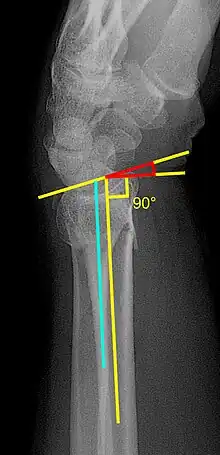

Various kinds of information can be obtained from X-rays of the wrist:[5]

Lateral view

- Carpal malalignment - A line is drawn along the long axis of the capitate bone and another line is drawn along the long axis of the radius. If the carpal bones are aligned, both lines will intersect within the carpal bones. If the carpal bones are not aligned, both lines will intersect outside the carpal bones. Carpal malignment is frequently associated with dorsal or volar tilt of the radius and will have poor grip strength and poor forearm rotation.[5]

- Tear drop angle - It is the angle between the line that pass through the central axis of the volar rim of the lunate facet of the radius and the line that pass through the long axis of the radius. Tear drop angle less than 45 degrees indicates displacement of lunate facet.[5]

- Antero-posterior distance (AP distance) - Seen on lateral X-ray, it is the distance between the dorsal and volar rim of the lunate facet of the radius. The usual distance is 19 mm.[5] Increased AP distance indicates the lunate facet fracture.[8]

- Volar or dorsal tilt - A line is drawn joining the most distal ends of the volar and dorsal side of the radius. Another line perpendicular to the longitudinal axis of the radius is drawn. The angle between the two lines is the angle of volar or dorsal tilt of the wrist. Measurement of volar or dorsal tilt should be made in true lateral view of the wrist because pronation of the forearm reduces the volar tilt and supination increases it. When dorsal tilt is more than 11 degrees, it is associated with loss of grip strength and loss of wrist flexion.[5]

Posteroanterior view

- Radial inclination - It is the angle between a line drawn from the radial styloid to the medial end of the articular surface of the radius and a line drawn perpendicular to the long axis of the radius. Loss of radial inclination is associated with loss of grip strength.[5]

- Radial length - It is the vertical distance in millimetres between a line tangential to the articular surface of the ulna and a tangential line drawn at the most distal point of radius (radial styloid). Shortening of radial length more than 4mm is associated with wrist pain.[5]

- Ulnar variance - It is the vertical distance between a horizontal line parallel to the articular surface of the radius and another horizontal line drawn parallel to the articular surface of the ulnar head. Positive ulnar variance (ulna appears longer than radius) disturbs the integrity of triangular fibrocartilage complex and is associated with loss of grip strength and wrist pain.[5]